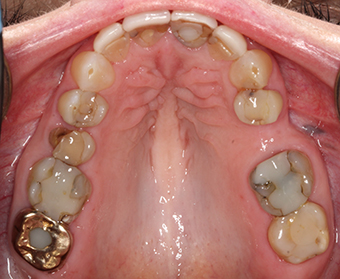

Before any major dental work, a dentist needs to check that your teeth come together properly when you bite and chew. This patient, who faced multiple problems with previous dental treatments, came to our office looking for a solution. The issue was an undiagnosed problem with her bite, which was causing the failure of her dental restorations. By using a specialized bite appliance to understand her bite, we created a plan that helped improve both the function and appearance of her smile.

A 68-year-old woman came to our office with broken teeth and a damaged veneer. She wanted her teeth to look longer, whiter, and prevent further chipping. She was also unhappy with the shape and colour of her front teeth. She had been experiencing bite issues, including jaw discomfort and tooth sensitivity, and had several previous failed dental treatments.

Our goal was to create a comfortable bite and improve the esthetics of her smile by: